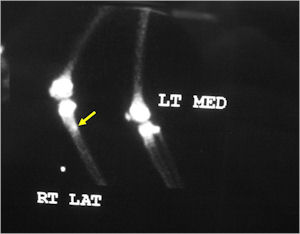

Bone Scan:

- Double Density Sign: Hot within the nidus and less intense accumulation peripherally within the sclerotic bone